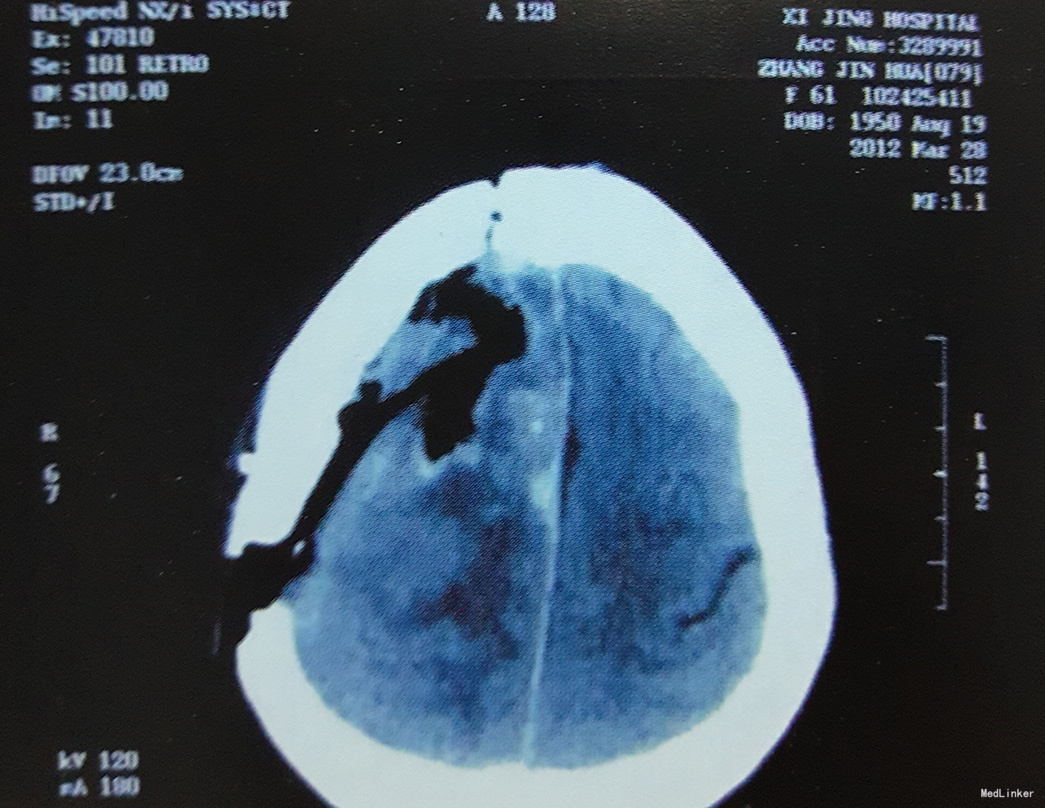

术前影像学检查:颅脑CT及MRI扫描示:右侧额顶部占位,强化效应明显,边界清,考虑脑膜瘤可能。

诊断:右额顶中央前回矢状窦旁脑膜瘤

术后复查颅脑CT示:肿瘤切除干净,周围水肿基本消失,大脑中线结构恢复正常